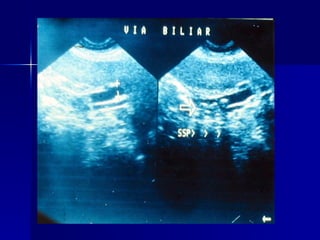

Ictericia datos paraclínicos: ULTRASONOGRAFIA COLELITIASIS, COLEDOCOLITIASIS DILATACIÓN DE LOS CONDUCTOS BILIARES CRECIMIENTO VESICULAR ENGROSAMIENTO DE LA PARED VESICULAR NEOPLASIAS DESDE 3 CENTIMETROS ENFERMEDAD PANCREÁTICA

Ictericia datos paraclínicos:ULTRASONOGRAFIA COLELITIASIS, COLEDOCOLITIASIS DILATACIÓN DE LOS CONDUCTOS BILIARES CRECIMIENTO VESICULAR ENGROSAMIENTO DE LA PARED VESICULAR NEOPLASIAS DESDE 3 CENTIMETROS ENFERMEDAD PANCREÁTICA